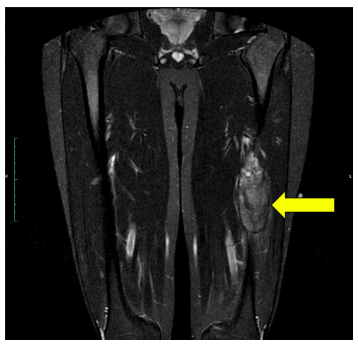

An example of an MRI depicting Ewing’s sarcoma in the lower extremity is shown.